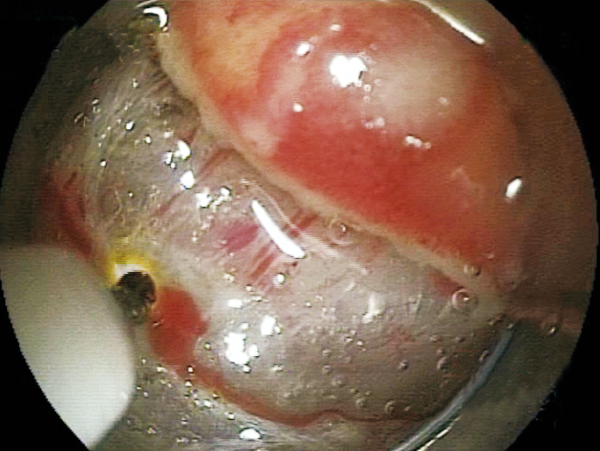

Clinical Image :Submucosal dissection

Clinical Image :Submocosal injection